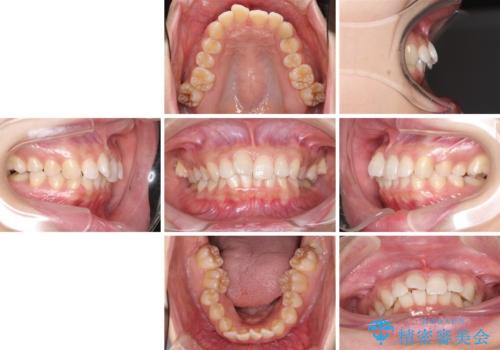

奥歯の倒れた歯を改善 インビザラインでの矯正治療

- 患者様

- 30代女性

- インビザライン

- 治療期間

- 2年9ヶ月

- 前歯のデコボコと奥歯の不正咬合を気にして来院された患者様です。

左右の大臼歯が全て鋏状咬合(シザーズバイト)になっており、治療が難航することが予想されましたが、インビザラインにより治療を行うこととしました。

最難関と思われたシザーズバイトは比較的短期間で解消されました。

しかし、治療中に2度の出産を経験され、治療期間は長くなってしまいましたが、咬みやすく、清掃しやすい歯列を獲得することができました。